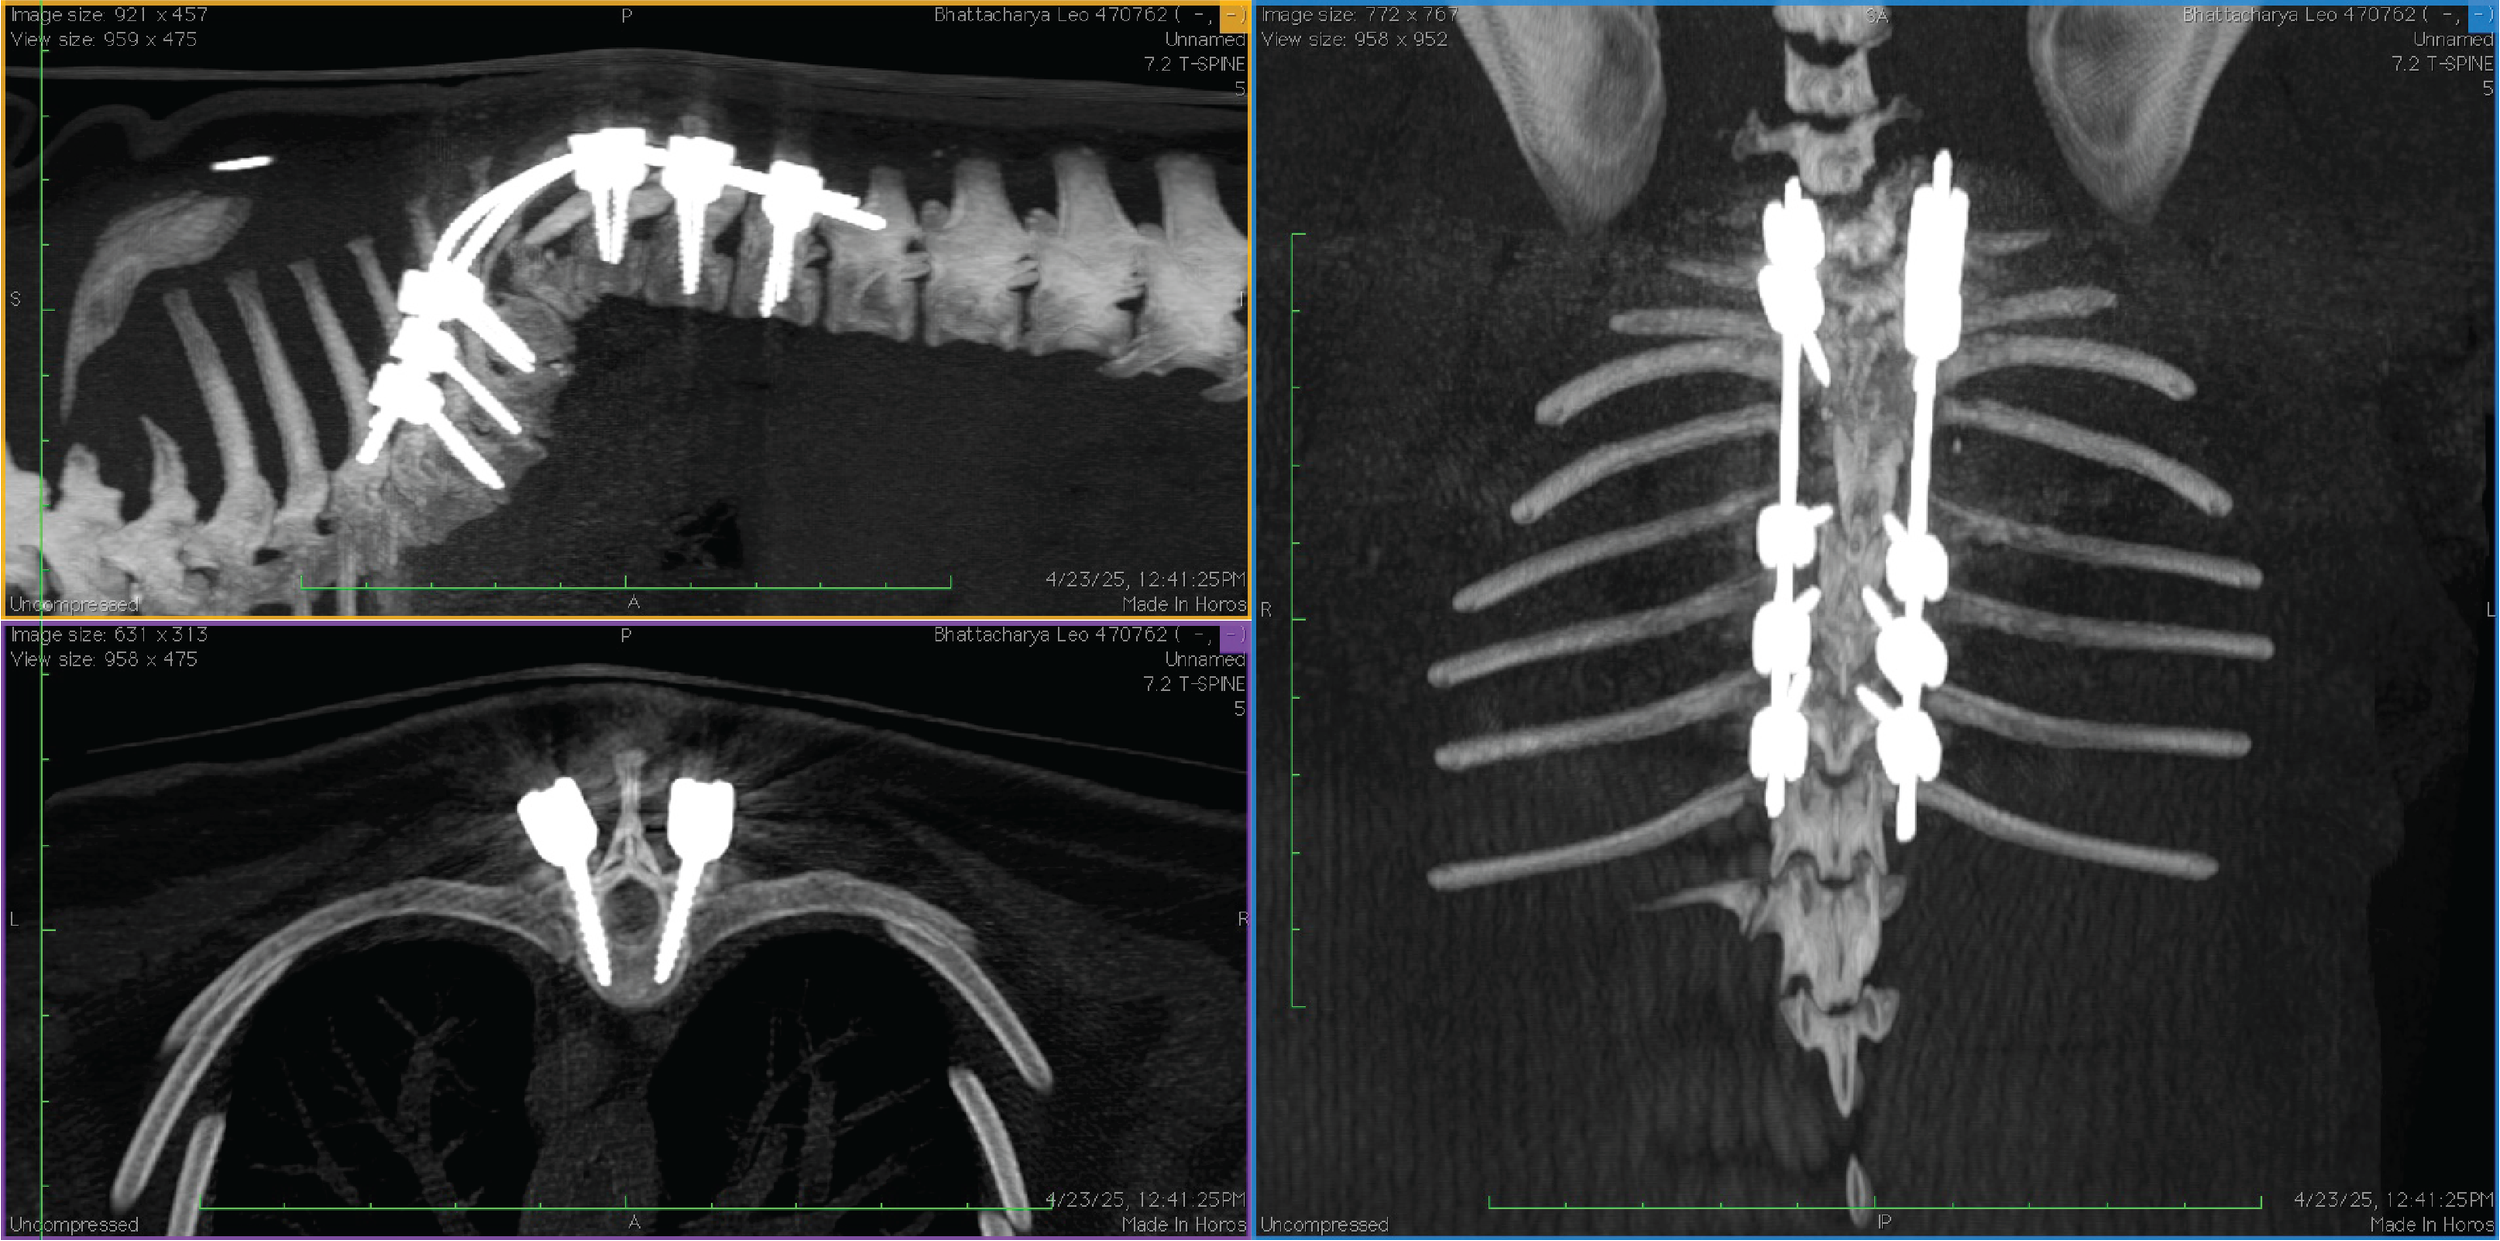

We start with an overview of polyaxial screws and how they are applied to the veterinary vertebral column. We cover fundamental biomechanics of vertebral column stabilization, screw trajectories and choosing the right screw size to build your construct.

The lab portion uses equipment from the Boreal Sciences, Bolt - Mini Polyaxial screw system along with a 3D printed model of a French Bulldog and Pug vertebral column. Participants will apply what they see in lecture to the spinal model.

We will show you the tips and tricks for successful construct engineering and spinal stabilization. From malformations to fractures and everything in-between thoracic, lumbar and lumbosacral stabilization.

This workshop / lab is designed as an introductory and advanced course to the use of polyaxial screws for vertebral column stabilization in dogs and cats. The course is for veterinary neurologists, surgeons and residents in neurology or surgery. The participant will gain knowledge on the fundamental biomechanics of the vertebral column and how to design and use polyaxial screws and rods to create a construct intended to stabilize a portion of the vertebral column. Specifically, the course will cover the thoracic, lumbar and lumbosacral vertebral segments. Attendees will use the laboratory portions of the course to design and build constructs on a 3D printed model of a French Bulldog Vertebral column. Advanced practitioners will use a high thoracic malformation model of a Pug, to engineer and create a construct.